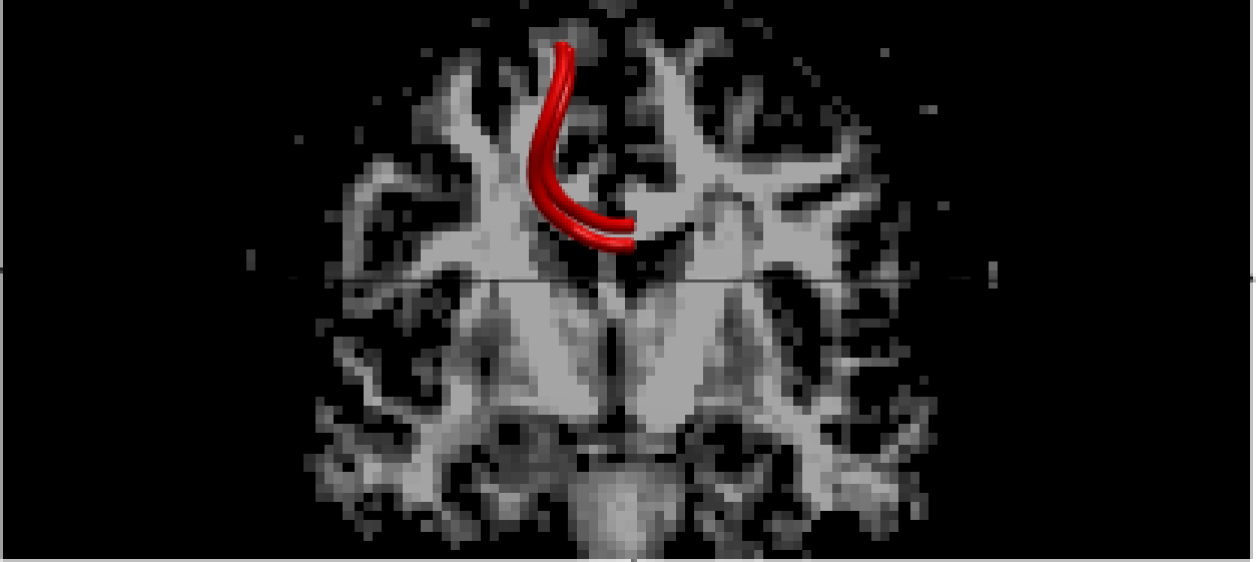

We use the IXI data-set provided by the Center for the Developing Brain, Imperial College London, to demonstrate our proposed method. The data-set is made available at the website https://brain-development.org/ixi-dataset/ under the CC BY-SA 3.0 license. From the data repository, we select the first 202020 healthy subjects collected from Hammersmith Hospital in London to demonstrate our methodological contribution and compare it to the benchmark method. We focus on the effects of body/weight index (BWI) on the two fibers located at the corpus callosum (see Figure 5). The covariate of BWI is scaled into [0,1]01[0,1].

Refer to caption

Figure 5: The figure illustrates the fibers the two fibers located at corpus callosum. The background is the Coronal plane of a human brain. The two red bundles are the fibers located in the region of interest.